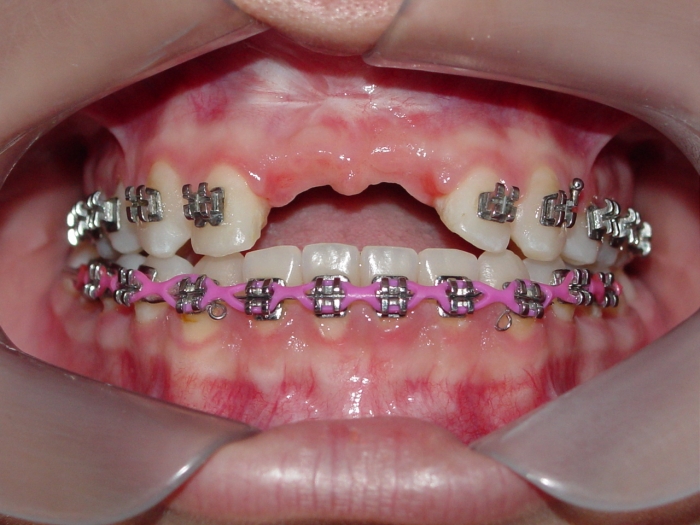

Protese Provisória sobre os implantes